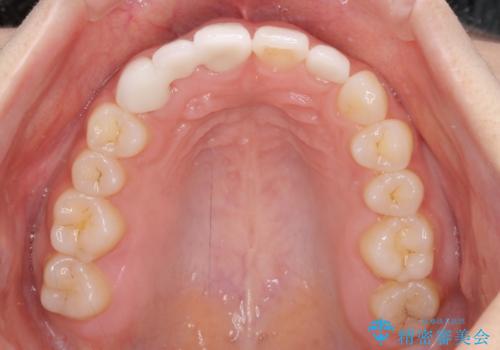

- 前歯の隙間を気にして来院された患者様です。

診察の結果、前歯が1本欠損しており、さらに矮小歯(通常よりも小さい歯)が1本存在していました。

欠損による前歯のスペースが大きかったため、事前にワイヤー矯正で前歯の位置を大きく動かし、その後は上下をインビザラインで整えることとしました。

矯正治療後には欠損部はオールセラミックブリッジに、矮小歯はオールセラミッククラウンにて補綴することとしました。

前歯のスペースは、堅い線維の通った歯肉があり、幅も大きかったことから、歯肉切除を行った上でワイヤー矯正により移動を行いました。また、上唇小帯も歯間部付近まで付着していたため、合わせて切除しました。

ワイヤー矯正により、インビザラインよりも早く、歯軸の向きもコントロールしながら移動させることができました。